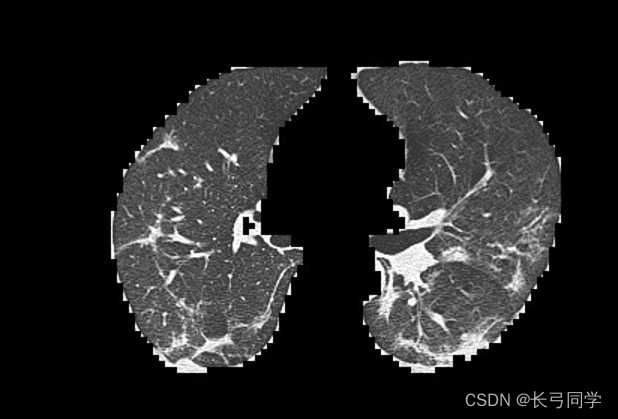

1. COVID-19肺炎肺部CT图特征简述(以下内容为查阅资料后整理,本人并非医学影像专业,如有错误敬请指正)主要为间质化改变,磨玻璃影2.数据预处理为减少GPU计算量,先使用crop函数裁去CT图黑边,并对图像进行resize(此处处理后的图片大小为420*290)训练集与测试集数据总数:traintestcovid-192289572normal15923983.使用卷积神经网络(CNN)参